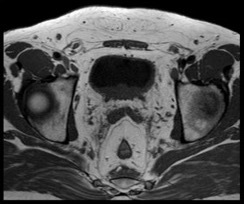

Cystitis cystica et glandularis (CCEG) is a rare hyperproliferative lesion of the bladder mucosa resulting from chronic inflammation or obstruction. It is marked by glandular metaplasia of transitional cells, leading to a cystic appearance due to the proliferation of Von Brunn islets, which cause invagination of the transitional epithelium into the lamina propria. Imaging characteristics are nonspecific and resemble those of a bladder mass. Cystoscopic findings typically show bullous edematous lesions or papillary lesions with gelatinous surfaces, often affecting the trigone area. The involvement of the trigonal region can complicate the identification of ureteric orifices, posing a risk of resection-related injury. Our goal is to highlight the clinical behavior, radiological and cystoscopic features, and propose a management algorithm to minimize deterioration of renal function.

45 patients were included, 95% were men, with mean age of 35 years. Most common presenting feature was lower urinary tract symptoms (90%), with hematuria (30%), flank pain in 10%. Seventy percent patients had uppertract changes. Imaging findings are consistent with bladder mass and cannot distinguish cystitis cystica from carcinoma of bladder. Thirty percent of patients had recurrence of lesions with average time to recurrence being 13 months. Ten percent of patients underwent ureteric reimplant.